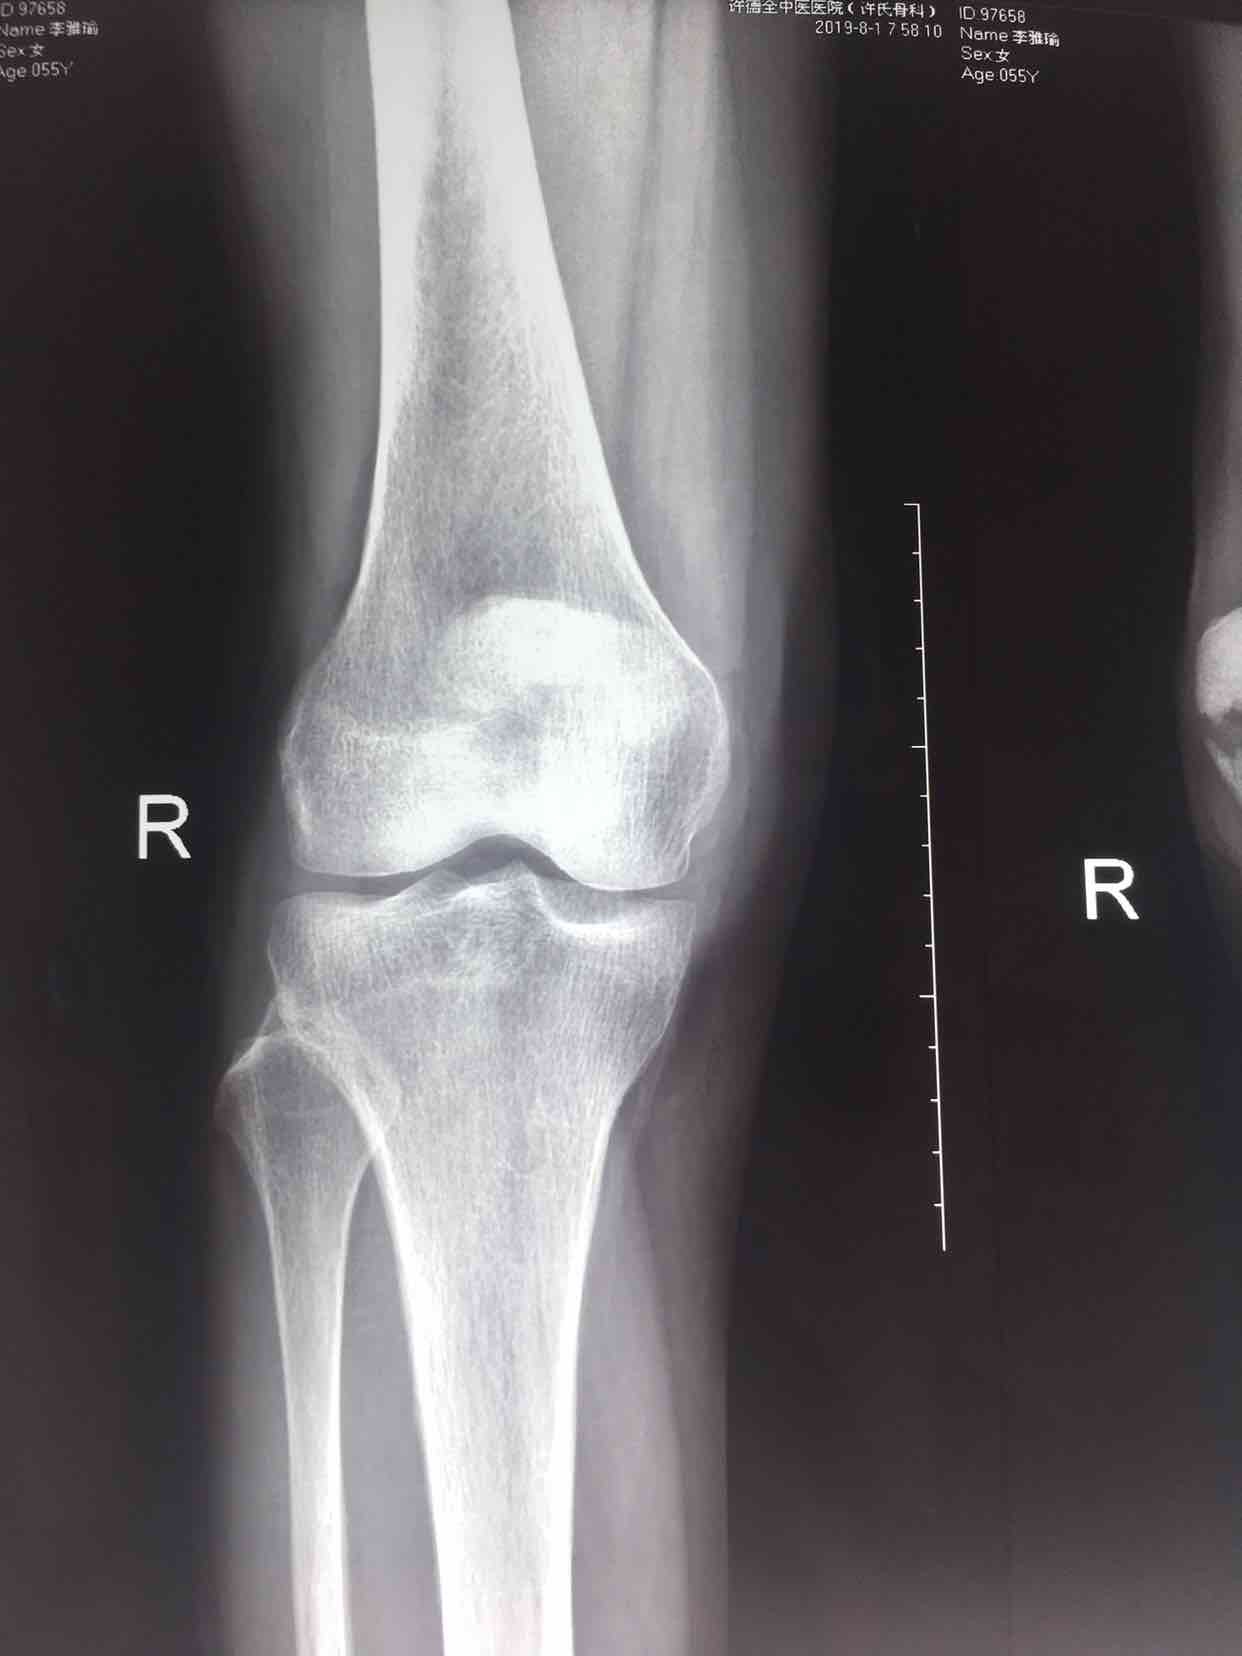

髌骨骨折(髌骨爪➕克氏针应用)

骨折 髌骨骨折

摔伤后右膝部肿痛,活动受限1小时入院。既往身体健康,无特殊不良嗜好。

生命体征平稳,心肺复未见异常。右膝部肿胀明显,皮色微红,皮温高,可及骨檫音及骨折断端,压痛明显,伸膝关节受限,末梢血运感觉正常。

诊断右髌骨骨折在腰麻下行切复内固定术,术后抗炎,消肿等处理。